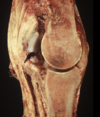

Subchondral cyst